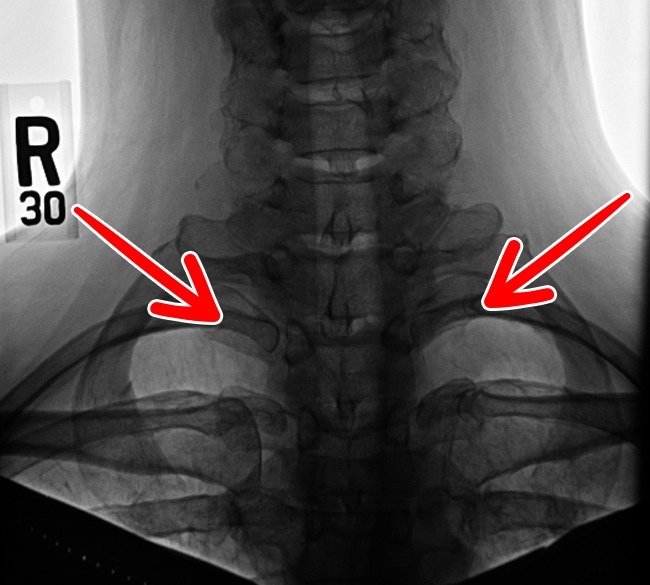

10. 第13對肋骨。

人類的近親—大猩猩和黑猩猩就有多一對肋骨,但人類通常只有12對,只有8%的成人會多一對肋骨。